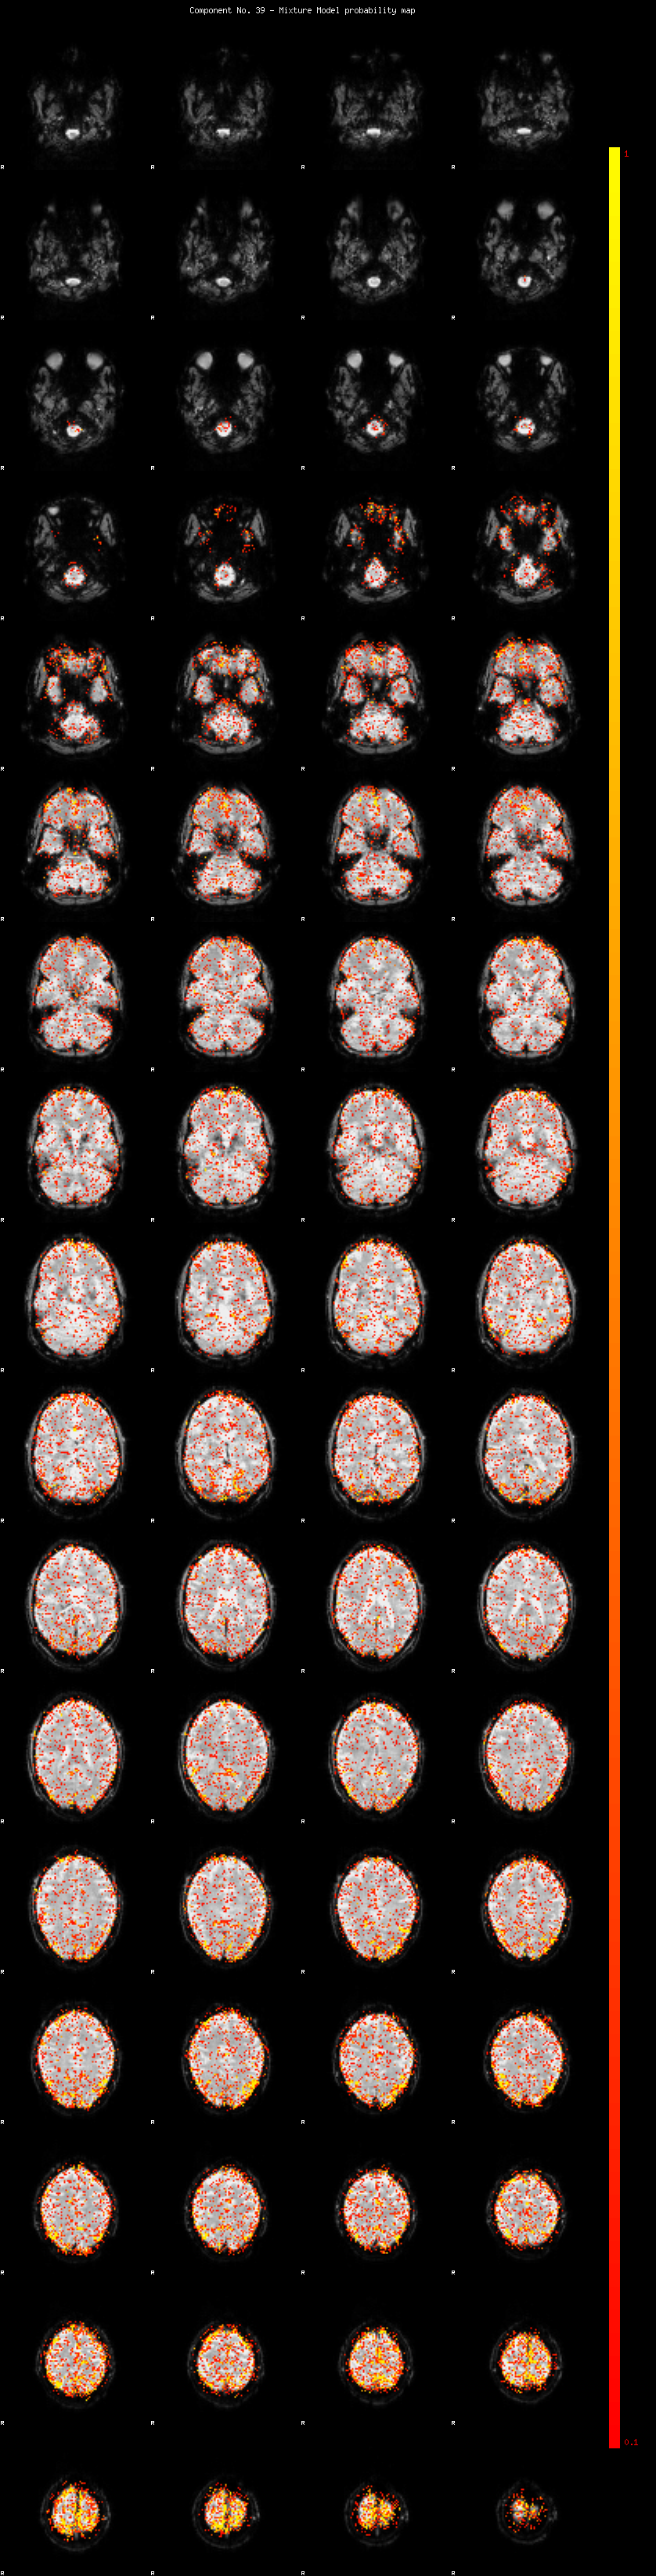

IC_39 Mixture Model fit

Means : 0.000000 2.493582 -2.361725

Vars : 1.000000 1.975249 1.050871

Prop. : 0.919924 0.052080 0.027996